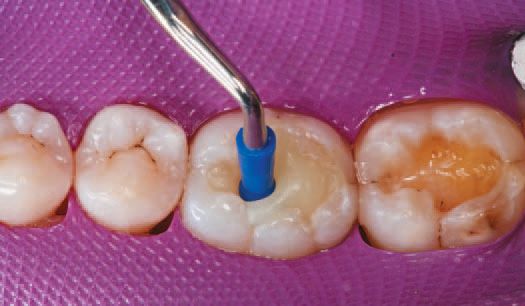

A single increment of Tetric EvoCeram Bulk Fill in shade IVA was then placed in the preparation of tooth No. 30 (Fig. 9), and shaped first with an OptraSculpt® sphere attachment (Fig. 10), then with an OptraSculpt pyramid attachment (Fig. 11). The final anatomy was contoured using a P1 plugger (Fig. 12). As a final step before finishing, the restoration was light cured with the LED curing light (Fig. 13).